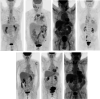

Methods: During the period of maximum incidence of the global pandemic in one of the most affected regions of Spain, there were 145 patients that met inclusion and exclusion criteria and were included in the study. Imaging findings previously described such as ground-glass opacities with low [18F]-FDG uptake were considered images suspicious for SARS-CoV-2 infection. Patients with these findings were referred to RT-PCR testing and close follow-up to confirm the presence or absence of COVID-19.

Results: Suspicious lung imaging findings were present in 7 of 145 patients (4.8%). Five of these 7 patients were confirmed as presenting SARS-CoV-2 infection, this is, COVID-19. In the remaining two, it was not possible to confirm the presence of COVID-19 with RT-PCR, although in one of them, PET/CT allowed an early diagnosis of a lung infection related to a bacterial pneumonic infection that was promptly and adequately treated with antibiotics.

Conclusion: These results confirm that the prevalence of SARS-CoV-2 infection is higher than suspected and that there are asymptomatic patients that are attending imaging departments to be explored for their baseline oncologic processes. In these patients, PET/CT allows an early diagnosis of COVID-19.